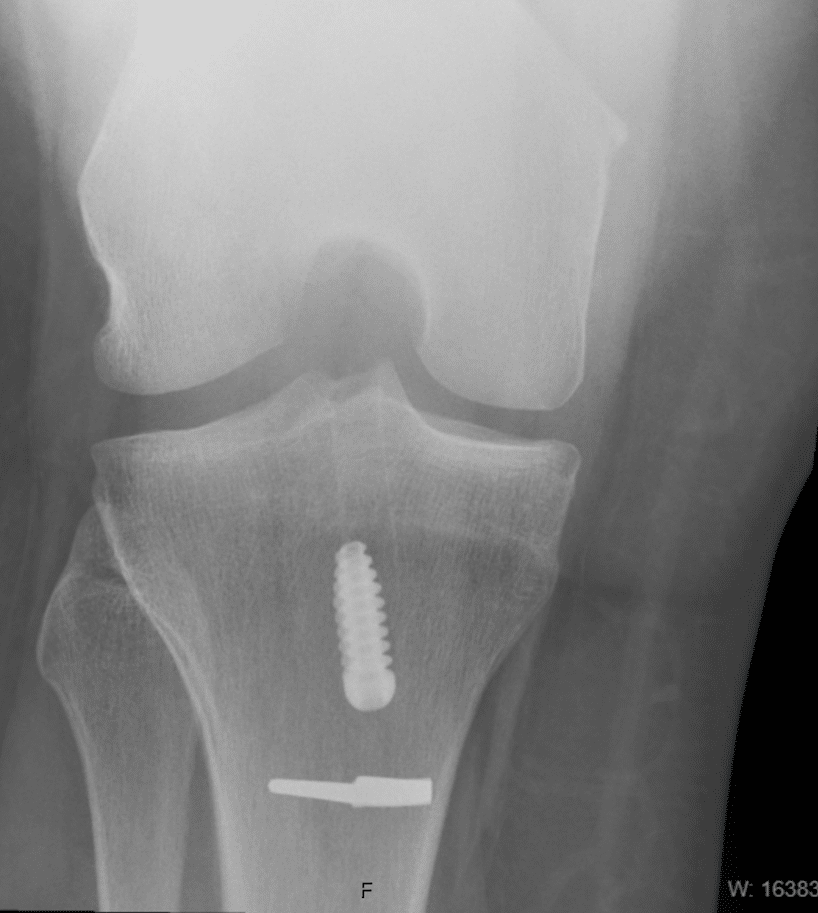

The surgery is completed with a combination of small incisions and arthroscopy assistance. Tissue for reconstruction is harvested from the same leg unless additional tissue is required. Synthetic graft or augments to graft may occasionally be used. The graft is secured through the knee joint with the use of staples and screws. Most patients go home the same day. Bruising and swelling are to be expected and elevation and Ice will help in the first 2-4 weeks.